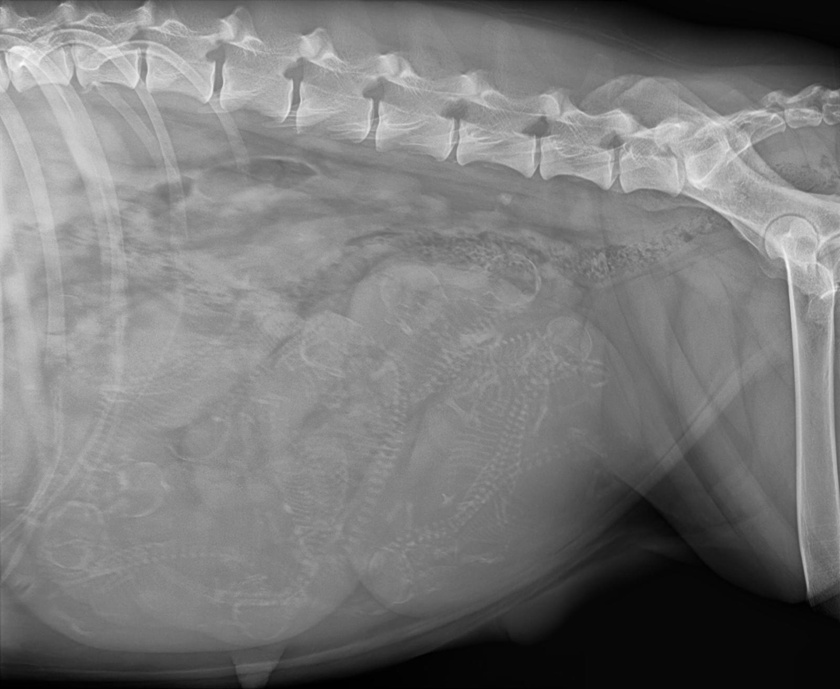

Das Röntgenbild zeigt regen Nachwuchs wir zählen 9-10

Wir erwarten unseren C-Wurf